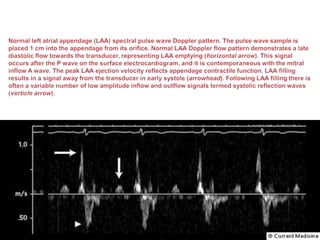

 Purpose of the left atrial appendage (LAA) is not fully understood.

 LAA acts as a capacitance chamber allowing sudden changes in LA

volume to be accommodated without marked increases in left atrial

pressure (LAP)

 The LAA acts as a cul-de- sac with a high incidence of thrombus

especially in the presence of atrial fibrillation (AF).

 The orifice of the neck of the appendage curves around the lateral

aspect of the LA between the left upper pulmonary vein (LUPV)

(posteriorly) and the junction of the LA and pulmonary trunk

(anteriorly).

 In LAA/LA clot except type Ia- most of the interventionalist usually

defer PTMC.

 For LA/LAA clot assessment we image LAA in mid esophageal 0

degree and 90-110 degree.

 Second image is obtained by slightly withdrawing TEE probe till

visualization of aorta and image LAA in 0 degree and 90-110 degree

angle with slight counter clock wise probe rotation.

 Severe rheumatic MS specially with associated AF, dilated LA(>4.5

cm),dense spontaneous ECHO contrast and LAA emptying velocity

<25 cm/sec is associated with LAA/LA clot.